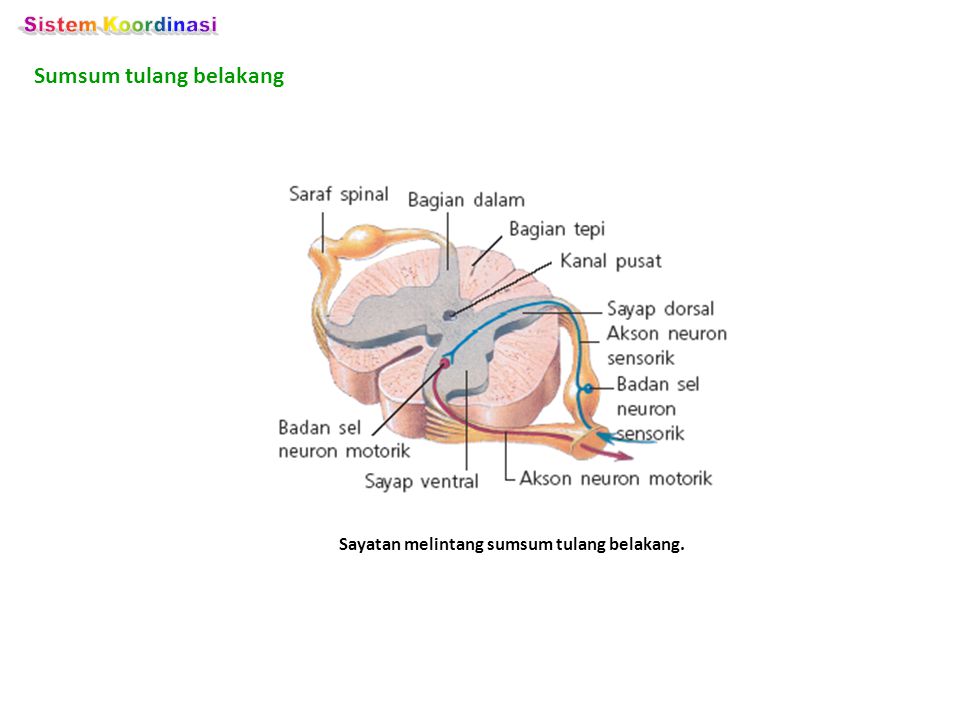

Sistem Saraf Pada Manusia Sistem Saraf Pusat Sistem

Sistem Saraf Pada Manusia Sistem Saraf Pusat Sistem